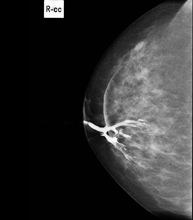

Mammography

Mammography tests use low-dose x-ray imaging to detect breast tissue pathologies (especially breast cancer) in gynaecological screening and targeted diagnostics. Mammography can be interventional with cyst puncture, stereotactic biopsy, pre-surgical marking, and galactography.

Digital mammography is an innovative breast examination technique that uses a low radiation dose, thus reducing exposure compared to conventional mammography. The image is digitised using special cassettes on a system known as CR (Computed Radiography). These digitalisation techniques provide excellent images, especially in breasts that are difficult to examine, such as glandular breasts, which appear dense on mammograms, enabling better detection of tumours in this group of patients.